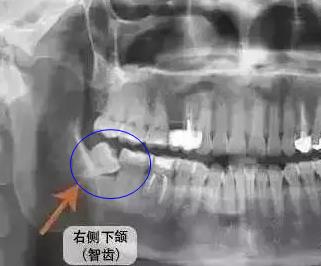

發炎的智齒拍片後情況

如果是齲齒疼痛,及時到醫院去除齲壞的組織,然後補牙充填;如果是牙齦炎牙周炎等牙痛,先到醫院洗牙、齦下刮治去除牙結石對牙齦的刺激;如果是智齒發炎疼痛,到醫院局部衝(chong) 洗上藥,注意清淡飲食,飯後漱口,炎症退卻後,及時拔除位置不正的智齒。